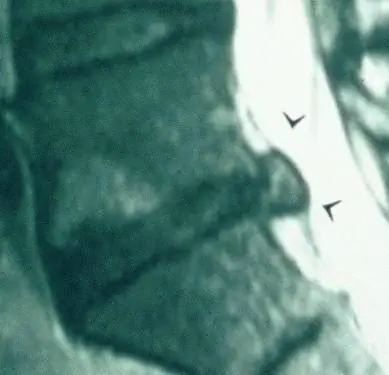

Выпячивания и травмы дисков можно устранить без хирургического вмешательства. Даже очень большие травмы диска, как на фото. Ниже представлены МРТ до и после моего пациента, у которого была огромная травма. Посмотрите на фото после, и вы увидите, как должен выглядеть позвоночный канал, затем на фото до, и вы увидите, что он большой. Похоже, кто-то чихнул на его МРТ, в спинномозговом канале столько хлама. Три месяца после той МРТ до полного избавления от травм диска - вот чего он добился.

Ниже приведен пример диска в процессе заживления. Выпуклость, похожая на воздушный шар, заживает и вернется в нормальное состояние. Этот процесс слишком сложен, чтобы полностью описать его в этой короткой статье, но когда я провожу курсы по реабилитации поясничного отдела позвоночника, я подробно описываю этот процесс.

Слева: раньше; Справа: после.